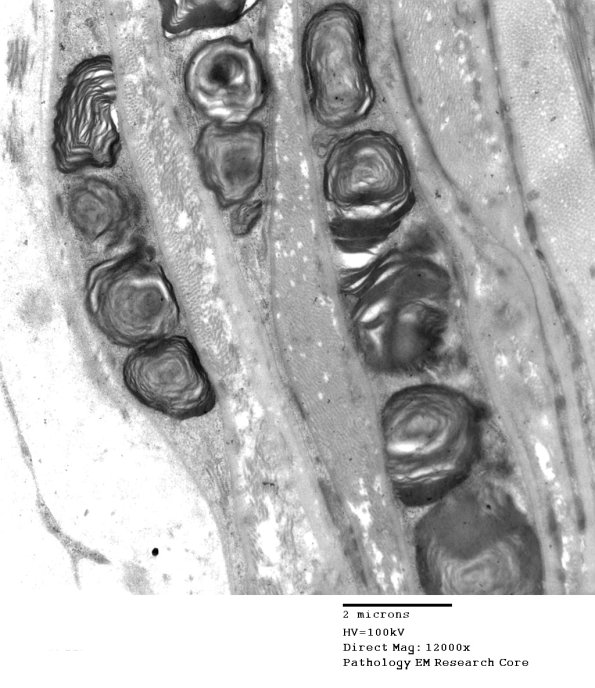

Perineurial inclusions at higher magnification. (electron micrograph)